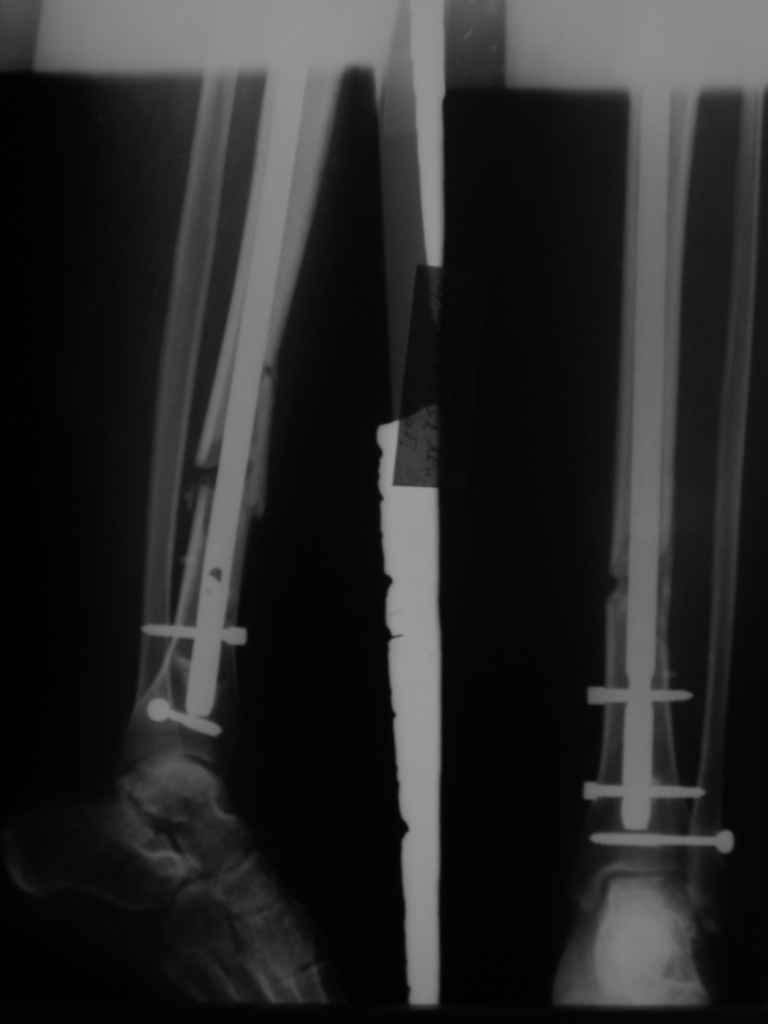

Re: неправильно фиксированный перелом

Вот именно количественный, т.е. сколько градусов в вальгусе допустимо и при каком диастазе в мм или в % от толщины диафиза.

Но почему решение динамизировать на сроке 8 недель с полным удалением всех проксимальных винтов даже не рассматривается Вами? Ведь тогда нагрузка с фиксатора будет снята, и переломов металла можно будет не бояться и наступать полной нагрузкой.

Все это к тому, что те, кто занимается гвоздями и Вы в том числе можете выложить не один снимок с подобными диастазами и вальгусами-варусами, где достигнуто сращение и не получено проблем. Тогда откуда такая "адназначность" врешении об реостеосинтезе?